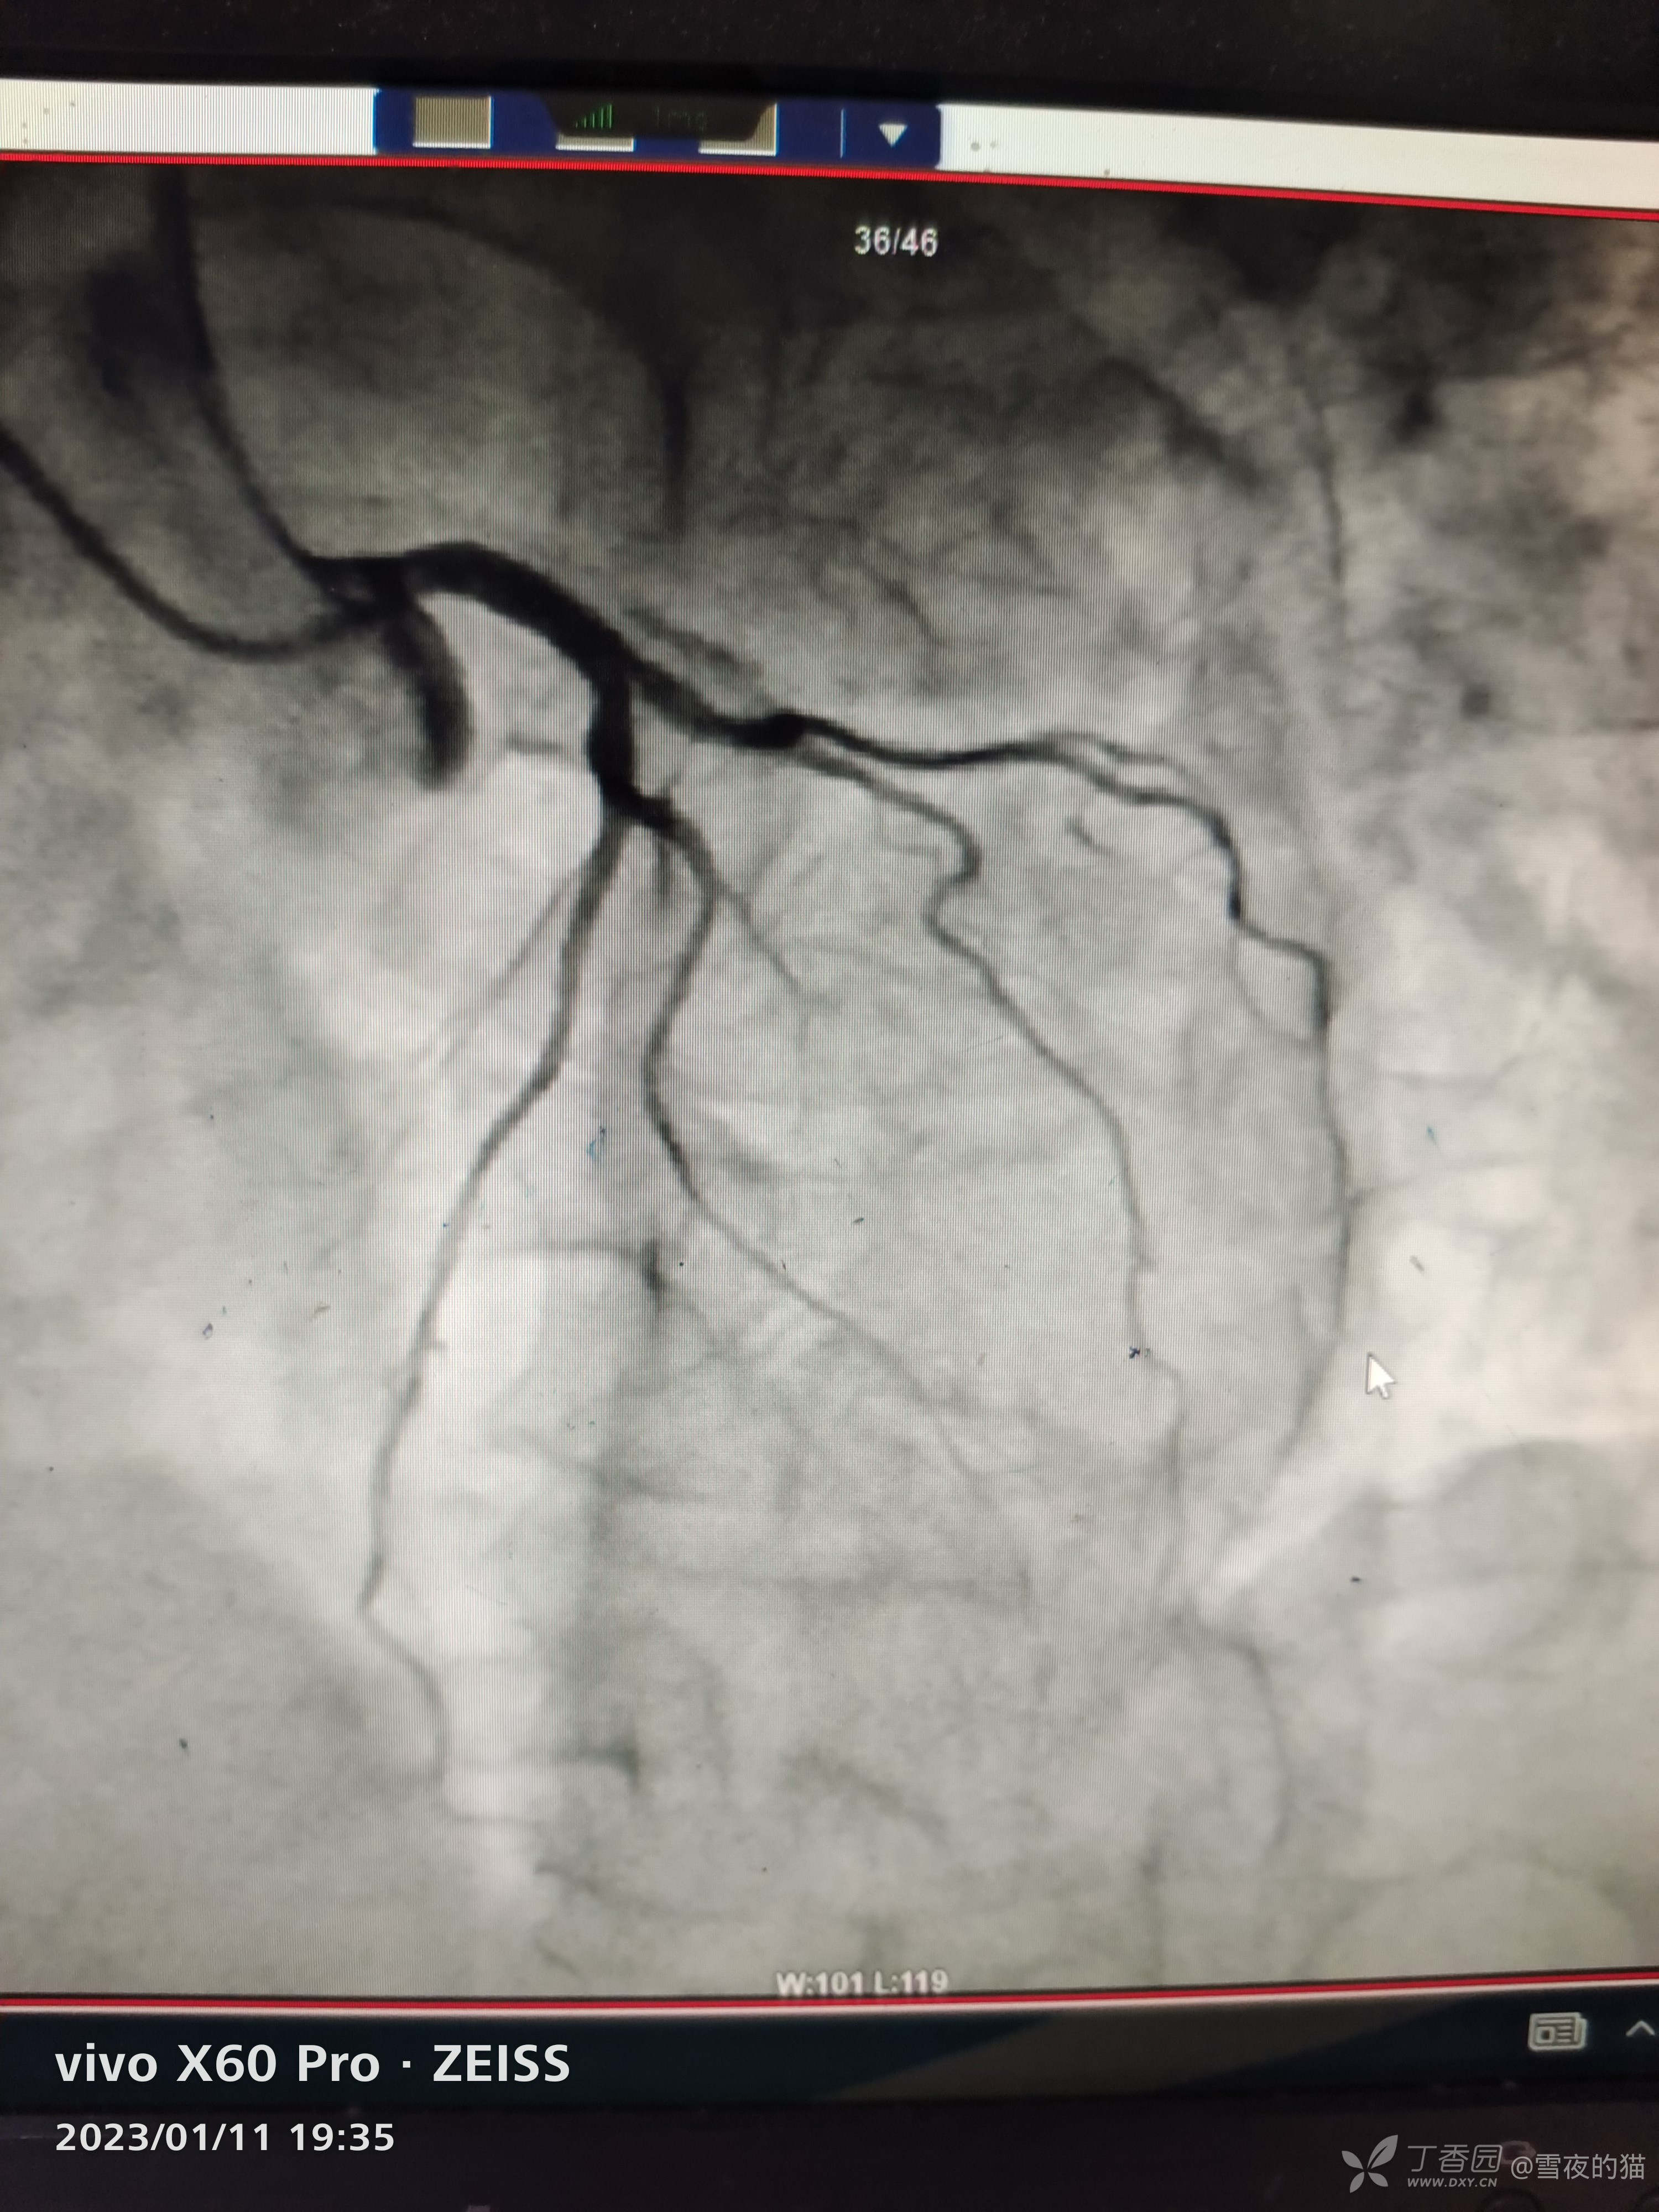

完善冠脉造影提示冠脉硬化,